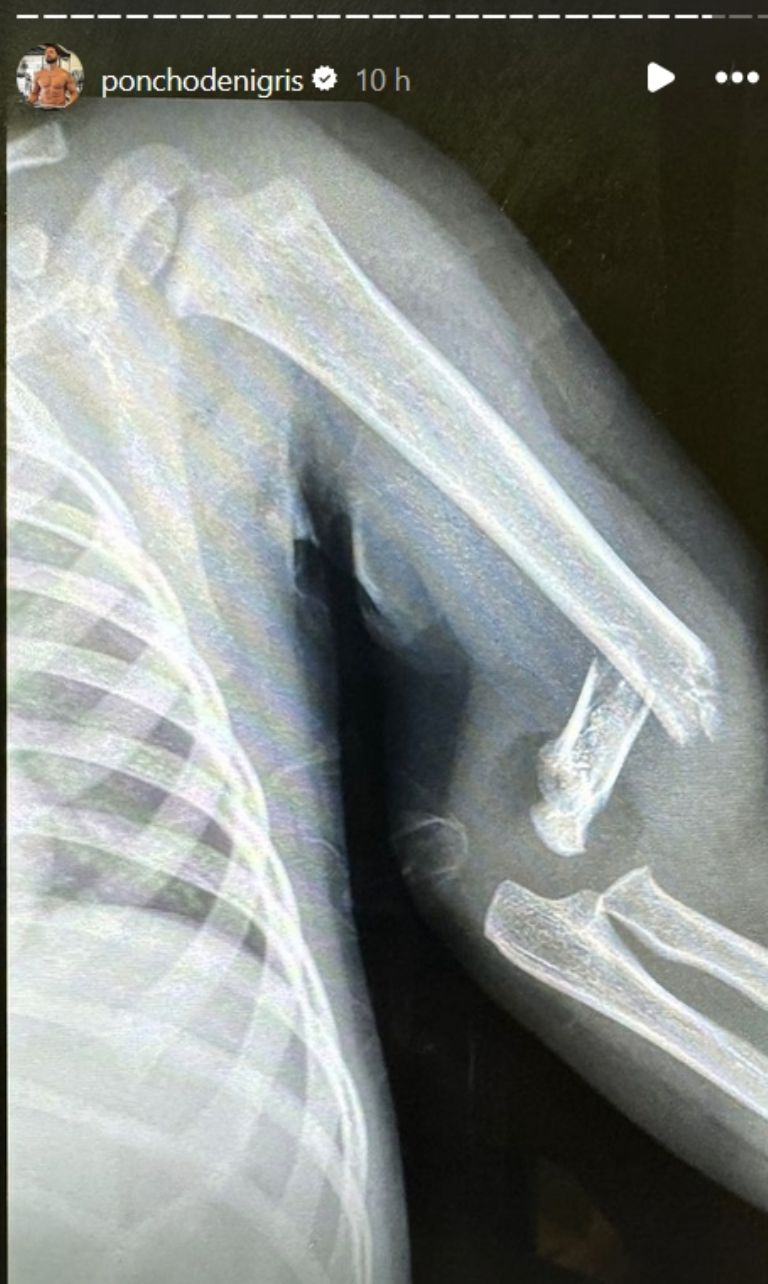

Como es bien sabido, además de ser empresario, actor, bailarín y conductor, De Nigris es padre de familia y cuenta con cuatro hijos (tres de ellos son muy pequeños todavía). Generalmente, se le puede apreciar conviviendo con sus vástagos o dándoles alguna lección de vida; sin embargo, recientemente el que se llevó el aprendizaje fue él, luego de que su hijo menor, Toñito, sufriera un accidente de tal magnitud que se le terminó rompiendo el brazo.

La historia la contó el propio Poncho a través de sus historias de Instagram, donde narró que su hijo estaba jugando en la calle con sus hermanos, cuando ocurrió el incidente del que no dio demasiados detalles, solo aclaró que, probablemente, había sido su culpa. Asimismo indicó que, la única razón por la que hizo pública la noticia, fue porque cuando llegó al hospital algunas personas comenzaron a grabarlo, así que no le quedó mayor opción que hablar.

Poncho contó que, cuando llegó al nosocomio, tenía a su “hijo cargando” y le restó importancia a la historia, declarando que el accidente que su pequeño sufrió fue uno que suele sucederle a todos, aunque para él se trataba de una experiencia nueva: “Tuvimos un accidente leve, lo que pasa con los niños, pero nunca nos había pasado… se quebró un bracito Toño por andar jugando en la calle, se me hace que error mío, se me hace”, declaró el amigo de Wendy Guevara.

El esposo de Marcela Mistral aclaró que no se trataba de una situación grave, aunque sí dejó en claro que él mismo sufrió de malestar cuando vio que su hijo había sufrido una herida tan notable como una fractura: “Se siente feo… se siente horrible porque por tu culpa, por nada, se quiebre el brazo de uno de tus hijos”, dijo la celebridad. Finalmente, De Nigris declaró que esta misma situación sirvió como lección también para sus otros hijos, para que fueran más cuidadosos al momento de salir a jugar.